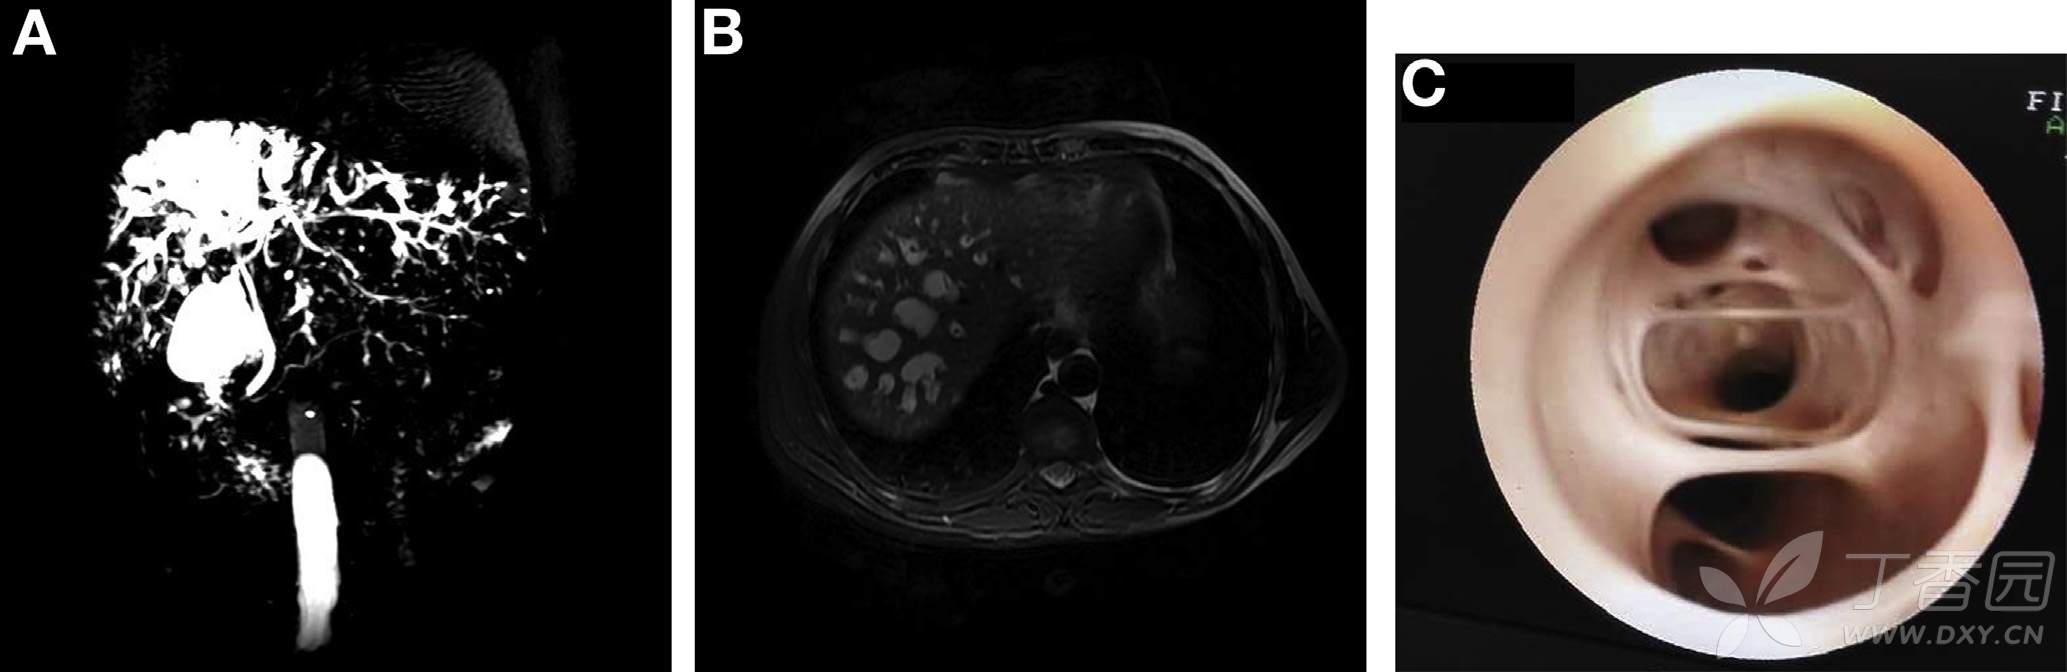

辅助检查:白细胞升高,TBIL、ALT、ALP、CA199轻度升高。乙肝病毒阳性,AFP阴性。MRCP显示右肝内胆管广泛囊柱样扩张(图A、B)。

患者行肝右叶部分切除术、胆囊切除、胆总管探查术、T管引流。术中可见肝脏呈花斑状,明显变硬肿胀。第7、8肝段大量囊性灶。术中胆道镜所见如图C。患者恢复良好,于术后10天出院。